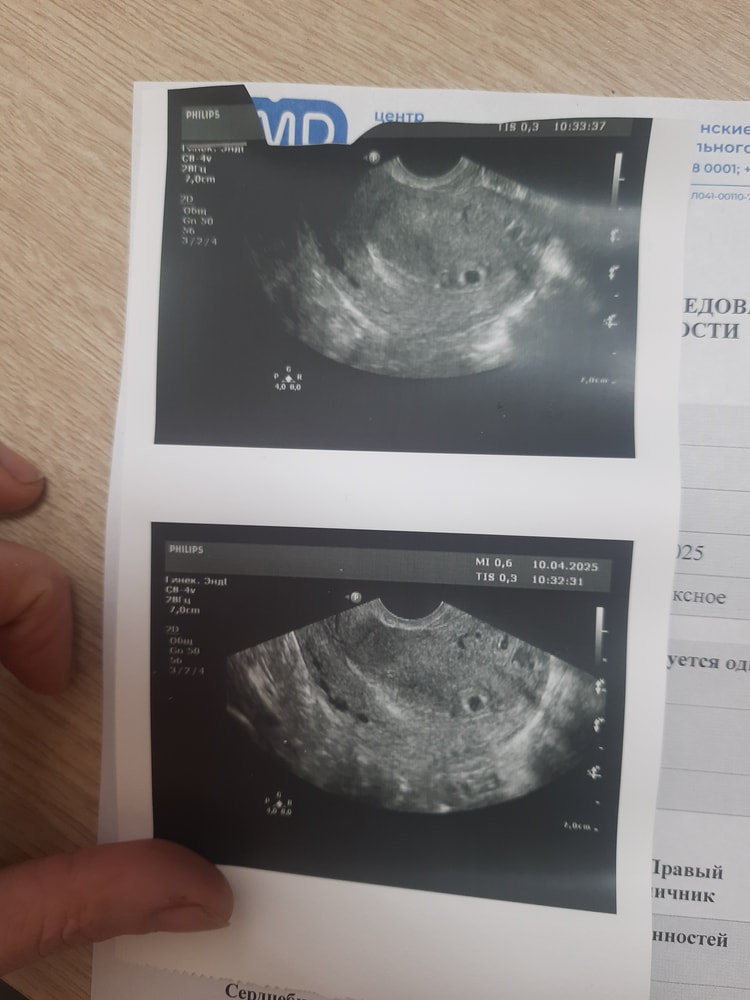

Вериока, смотрели, что эмбрион прикрепился в матке, чтобы исключить внематочную.

Замерили желтое тело, размер плодного яйца, посмотрели эндометрий и длину шейки матки.

На 11дпо хгч был 48.88

На 13 дпо - 143.38

На 17 дпо 958.03